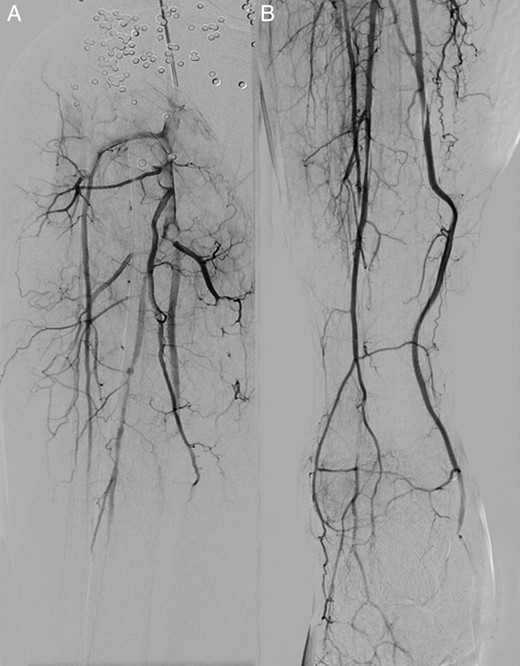

A repeat angiogram after 24 h of thrombolysis demonstrated improved patency while at 48 h excellent patency of the infragenicular vessels was seen (Fig. 2), and the patient was subsequently discharged on dual-antiplatelet and statin therapy. A follow-up arterial Duplex performed at 6 weeks post discharge demonstrated excellent patency of the stent graft and infragenicular arteries.

A digital subtraction angiogram at presentation (A) and after 48 h of continuous alteplase thrombolysis (B) demonstrating the improved patency of the infrapopliteal arteries.